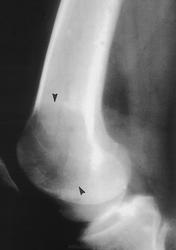

Гигантоклеточная опухоль.

Злокачественная гигантоклеточная  опухоль возникает из доброкачественной (частота 10-20%). После операции возможно появление рецидива опухоли.